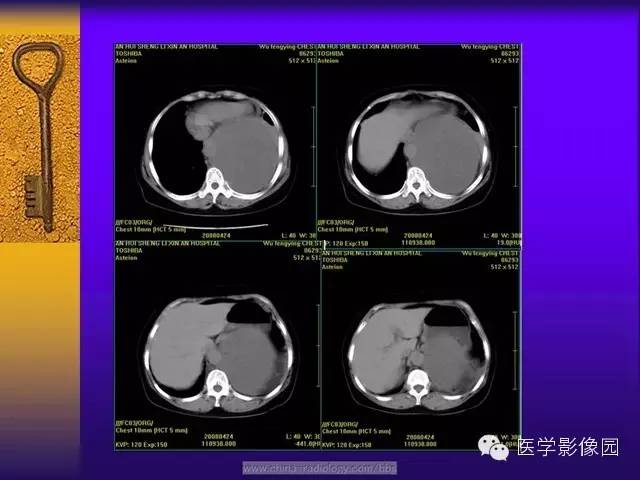

CT 平扫肿瘤密度以不均匀居多,肿瘤体积较小时密度可较均匀,随着肿瘤体积的增大其内部或周边可出现大小不等的低密度区,肿瘤越大坏死囊变的区域越大,形态越不规则。这与肿瘤细胞、胶原纤维的分布及二者发生玻璃样变、黏液样变及坏死囊变有关。肿瘤的供血血管由边缘向肿瘤内部延伸,肿瘤中心易出现血供不足而出现坏死、囊变。肿瘤越大坏死囊变的区域越大,形态越不规则。